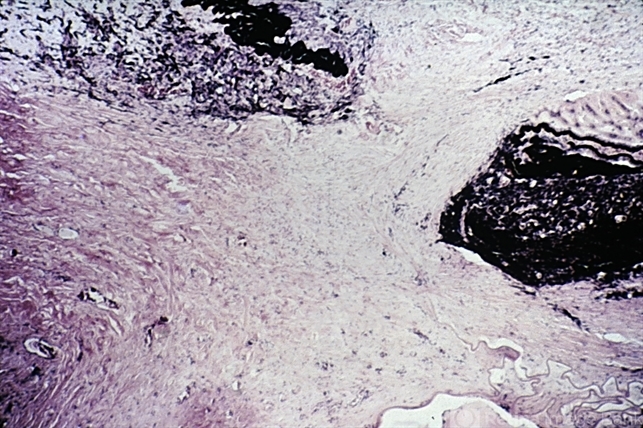

- Fibrous downgrowth, peripheral iridotomy

- Fibrous downgrowth. Fibrous tissue extends through the iridectomy site into the posterior chamber.